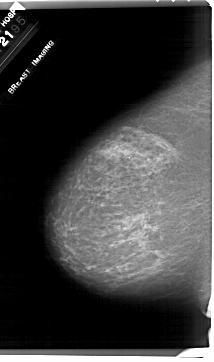

A_1917_1.LEFT_MLO

LEFT_MLO LINES 6361 PIXELS_PER_LINE 3901 BITS_PER_PIXEL 12 RESOLUTION 43.5 NON_OVERLAY